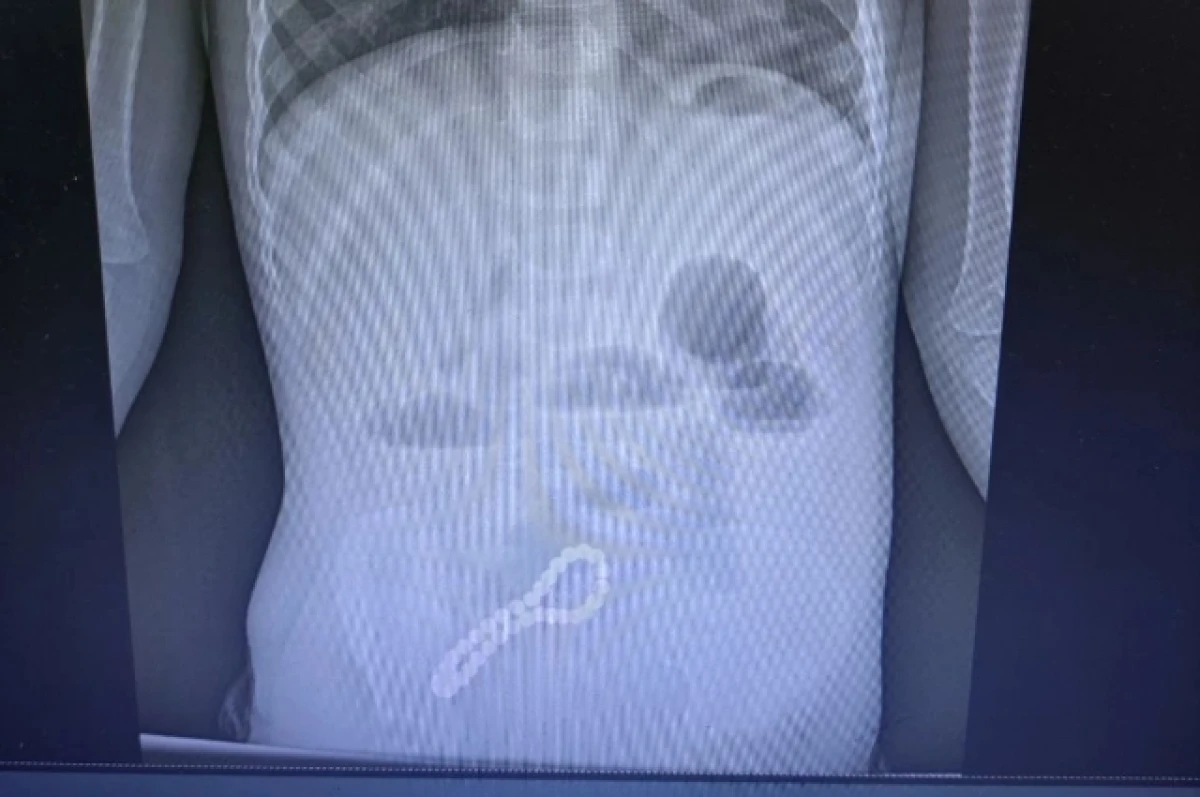

Орусиянын Рязань шаарында дарыгерлер шашылыш операция жасап, 30 шурусу бар магниттик билерикти кокустан жутуп алган үч жашар баланын өмүрүн сактап калышты. Бул тууралуу чет элдик басылмалар жазып чыгышты.

Жаш бейтап шашылыш түрдө балдар клиникалык ооруканасына жеткирилген. Рентген баланын ичегисинде бөтөн заттын бар экенин ачык көрсөтүп, тезинен хирургиялык кийлигишүүнү талап кылган. Дарыгерлер тобу тезинен операция жасоону чечишкен, натыйжада минилапаротомия жасалган - бул билерикти курсактын алдыңкы дубалындагы кичинекей кесик аркылуу алып салуу процедурасы.

Рязань облусунун башкы хирургу Олег Ларкин түшүндүргөндөй, магниттер бири-бирине коркунучтуу түрдө тартылып, ичегилердин биригишине алып келген.

Операция ийгиликтүү аяктагандан кийин, бейтаптын абалы туруктуу жакшыра баштаган жана азыр анын өмүрүнө коркунуч жок.